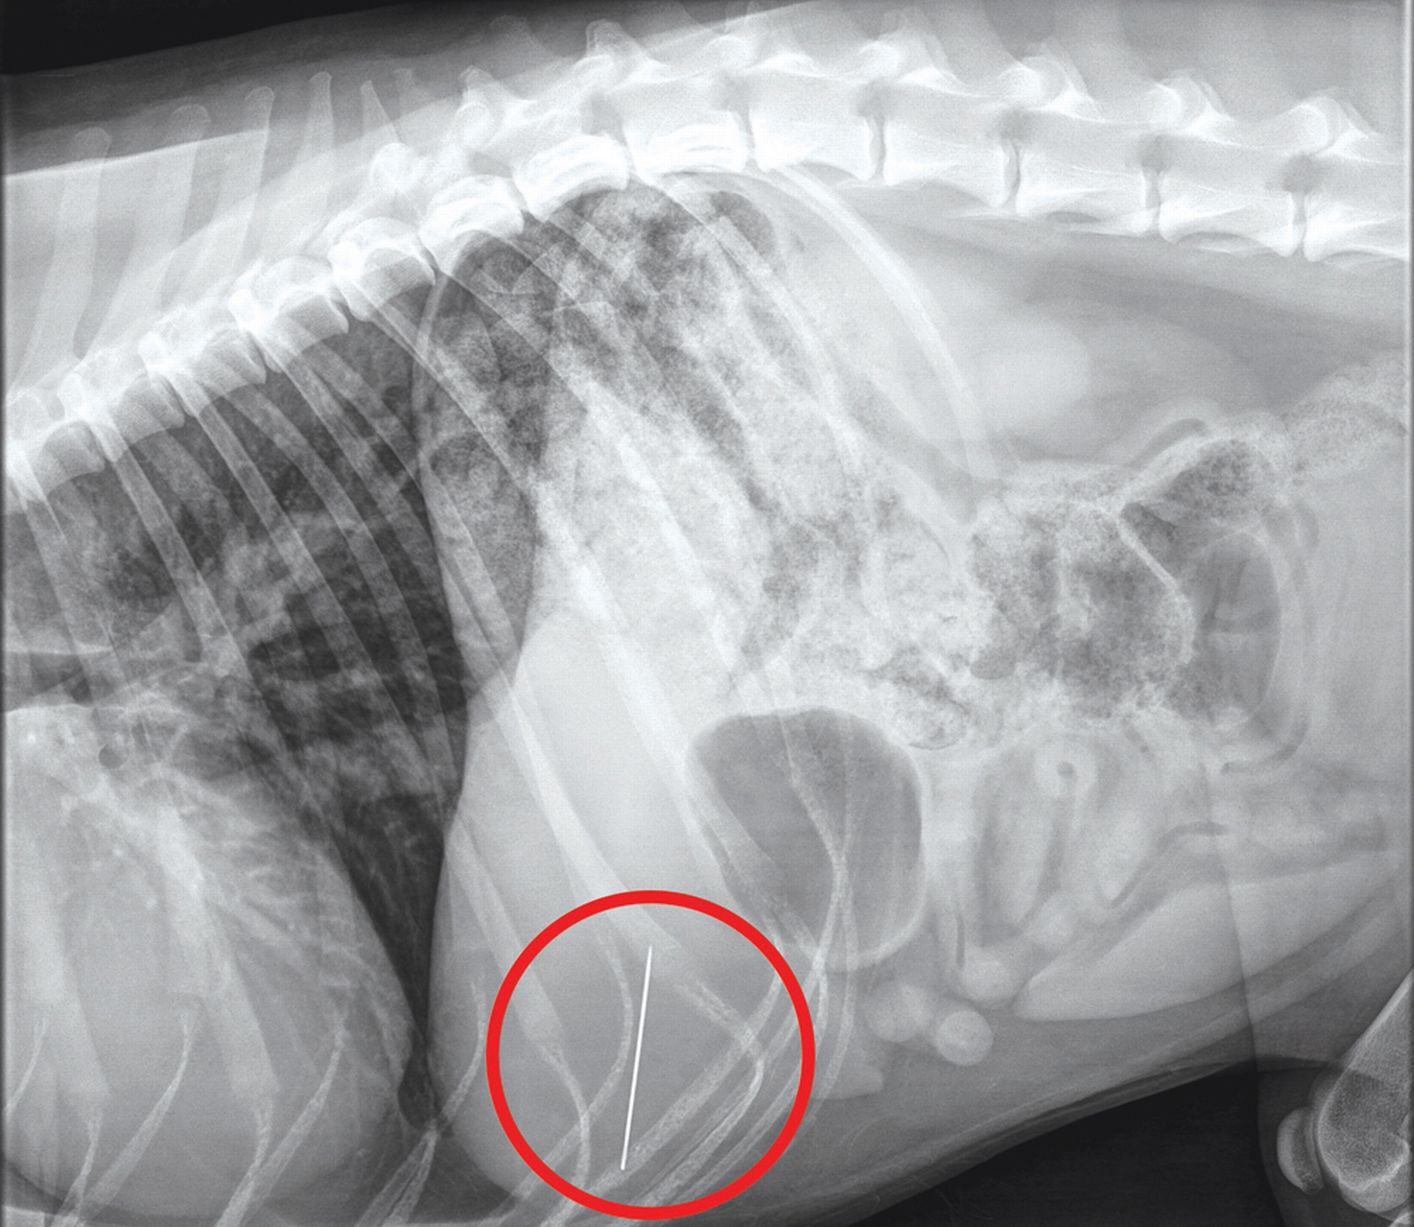

Increíble: Encontraron una aguja de coser de 4 cm en el interior del

Source: www.seamosmasanimales.com